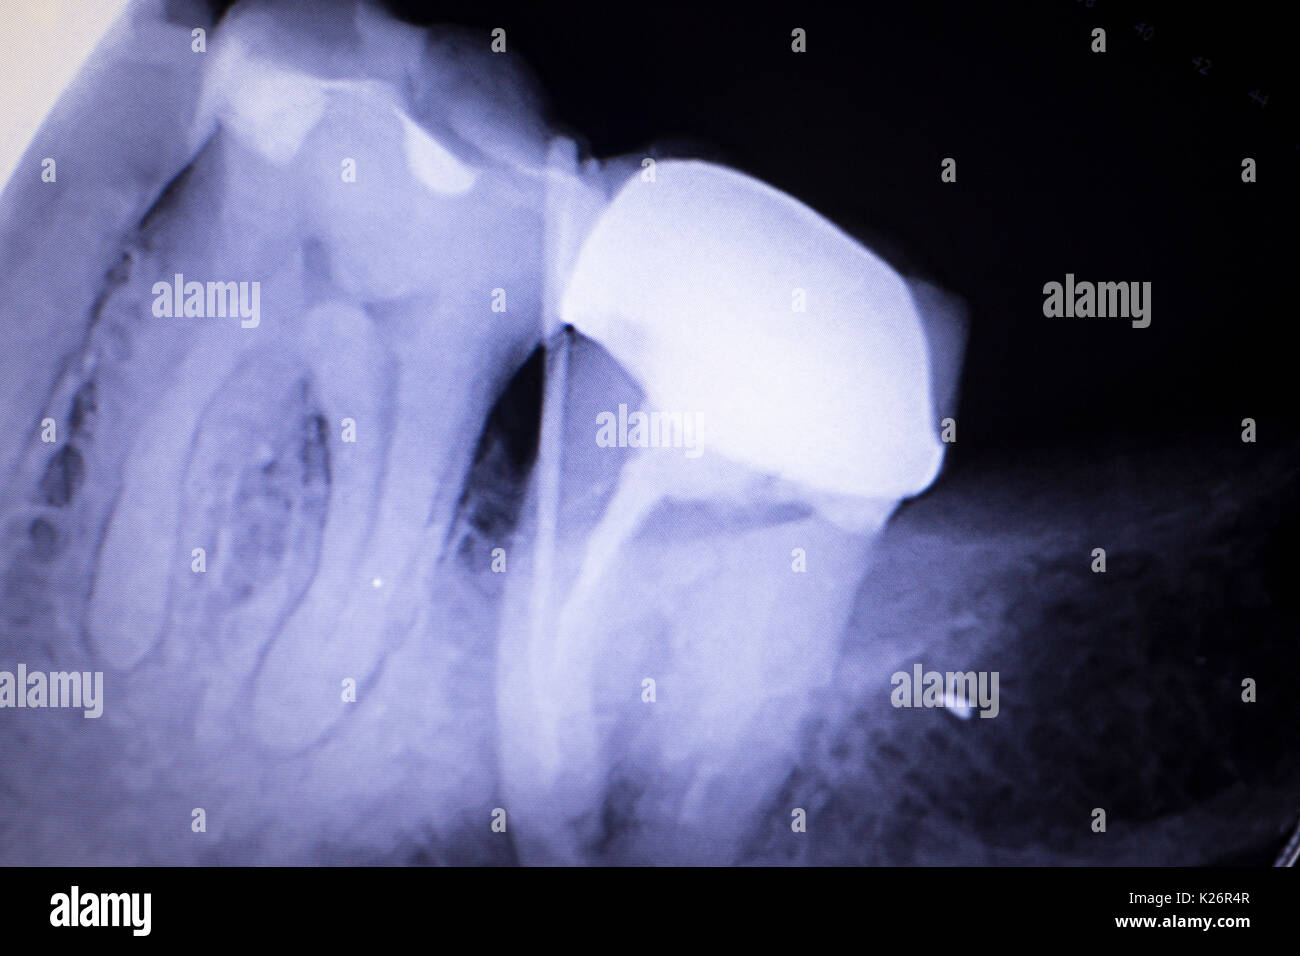

Dental xray test scan of tooth with crown filling and root canal

Dental xray test scan of tooth with crown filling and root canal X Ray Of Tooth With Filling Here is a picture of what a different tooth with decay underneath of an existing filling looks like. For example, under a filling, or between the teeth. Cavities are caused by decay and bacteria that break down the tooth’s enamel, eventually forming a hole or a cavity, which requires a dental filling to fix. Your honest dentist will try to. X Ray Of Tooth With Filling.